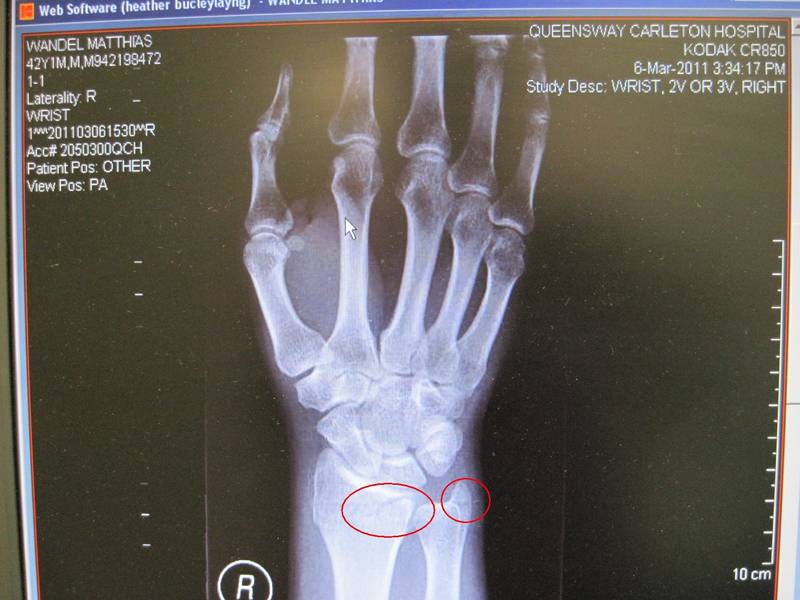

X-rays revealed that I had broken my wrist. It wasn't a displaced sort of fracture, but I did break the distal radius and the ulna styloid (see circles). It turns out that this type of fracture is very common, although it usually happens from falling onto outstretched hands. It mostly happens to kids and the elderly. Healthy adult's bones don't break as easily. I guess getting one's arm pinned between two cars is a bit unusual.